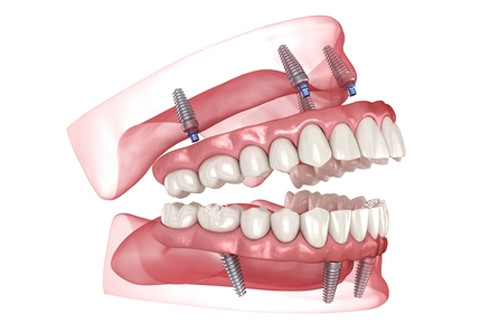

时间控制:单颗种植约20分钟,全口种植(All-on-4)约2小时。

all-on-4全口种植牙模型图